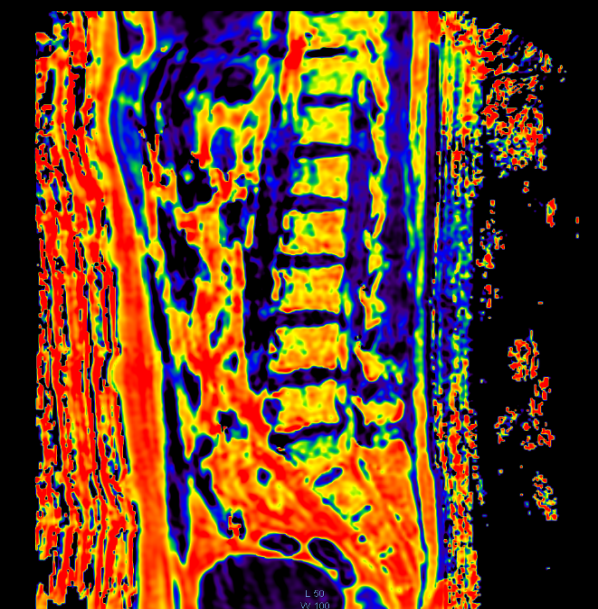

扫描完后,可以直接得到脂肪分数Fat Fraction图,在这个图上划ROI即可进行测量,得到脂肪含量分数。也可以把这个图转化为伪彩色,即可肉眼观察,又可以定量测量。

图中把色阶赋予值,分辨率是0~100,代表脂肪分数。如图所示,腹壁,内脏周围等,脂肪含量高的地方,在伪彩图上越红,测量得到的值一般是在86~93%;而脂肪含量低的地方,在图中颜色越深越蓝。